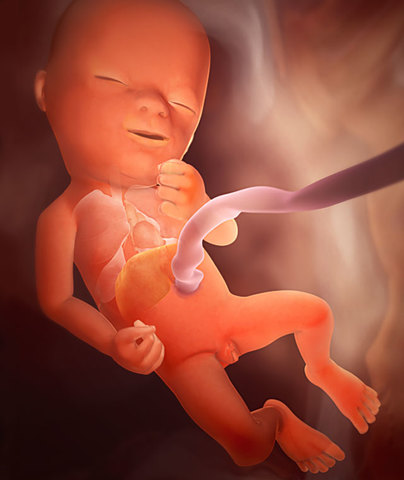

• Week 17

Week 17

The fetus now weighs approximately 5 ounces and is 5 inches in length (9 inches stretching out). The umbilical cord is stronger and thicker and its' retinas are becoming sensitive to light. Also, stool is starting to form as well.